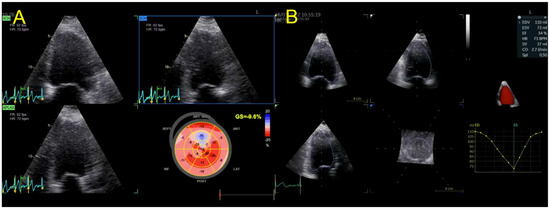

| Echocardiography | Hypokinetic non-dilated cardiomyopathy LVEF = 42% Mild mitral regurgitation IAS aneurysm | Hypokinetic non-dilated cardiomyopathy LVEF = 34% Mild mitral regurgitation IAS aneurysm | Left ventricular concentric hypertrophy LVEF = 54% |

| Cardiac magnetic resonance imaging | Hypokinetic non-dilated cardiomyopathy Left ventricular non-compaction LVEF = 50% | Hypokinetic non-dilated cardiomyopathy Regional sub-epicardial fibrosis LVEF = 41% | Not carried out |

| Management | CV risk factor control HTN treatment optimization Clinical and echo follow up | CV risk factor control HFrEF treatment optimization Clinical and echo follow up after 3 months of OMT | CV risk factor control Cessation of steroid use Clinical and echo follow up |